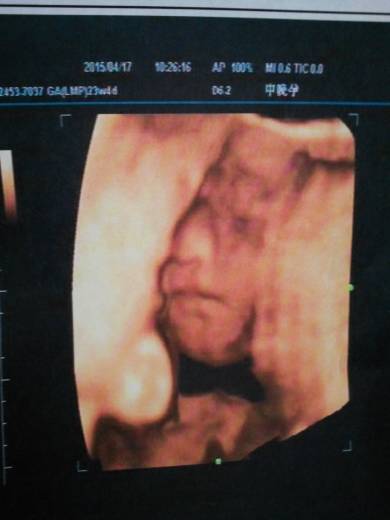

今天去做了四维彩超,孩子一切都好,是个男宝,前段时间胎盘前置,今天去检查,长上去了

你好,怀孕22-26周是四维彩超检查的最佳时间,四维彩超还能多方位、多角度的观察宫内胎儿的发育情况,为早期诊断胎儿先天畸形等疾病提供准确的科学依据。